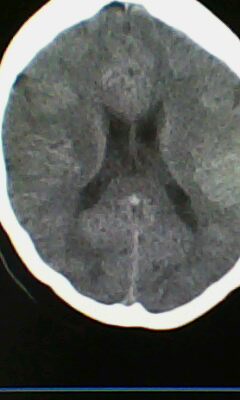

标题: CT25171:患者间断性头痛 无外伤史 [打印本页]

标题: CT25171:患者间断性头痛 无外伤史

右侧额叶脑穿通畸形囊肿。

右侧额叶脑穿通畸形囊肿。支持!